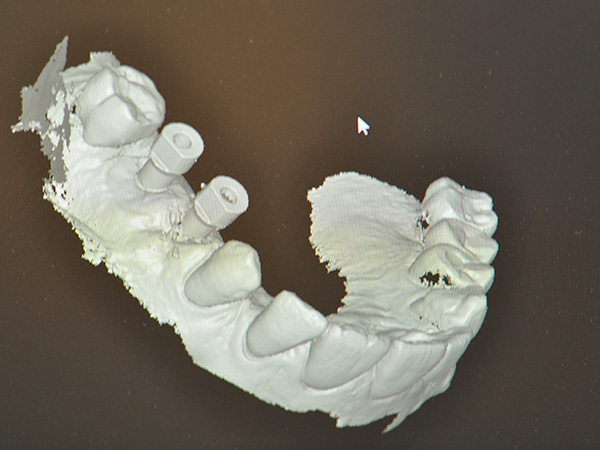

L’intervento ha previsto la progettazione di un impianto a carico immediato con sviluppo protesico digitale. Nello specifico, sono stati utilizzati i seguenti strumenti e tecnologie:

- Telecamere intra orali

- Software CAD 3D e macchina fresatrice CAM. La macchina permette di ricostruire il dente, impiegano le informazioni restituite dal software.

- Librerie aperte fornite da AZ Implant